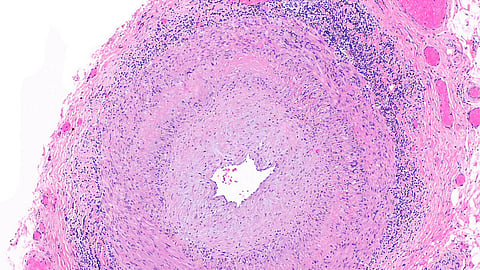

A common medication already used for autoimmune diseases such as rheumatoid arthritis is effective for patients with giant cell arteritis, according to findings from a team at the Perelman School of Medicine at the University of Pennsylvania published in the New England Journal of Medicine. [1] Causing the body’s immune system to attack blood vessels in the head, neck, and other areas, giant cell arteritis often leads to headaches, vision loss, and even aortic aneurysms. But nearly half of patients taking upadacitinib in a new Phase 3 clinical trial achieved sustained remission— while reducing their dependence on glucocorticoids (typically called “steroids”), the most common treatment. By comparison, less than 30 percent of patients who took a placebo achieved remission.

The side effects of treatment with glucocorticoids negatively impacts most patients with giant cell arteritis, often severely. Having the option to use upadacitinib for this disease is a big win because it could help patients stop taking glucocorticoids, control their disease, and improve their quality of life.